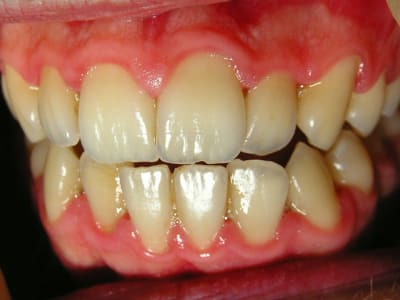

...Et les photos prises aujourd'hui, juste avant la séance de démonstration du contrôle de plaque.

Je n'ai pas fait de microscope durant cette séance car on sort tout juste du traitement antibiotique et ça n'aurait certainement pas montré grand chose.

Le but est de le revoir dans un mois pour déterminer sa motivation et son efficacité en matière de contrôle de plaque. Et pour voir comment la flore recolonise le terrain avant de lithotritier.

moi j'ai tendance à dire qu'initialement le controle de plaque n'était pas si mauvais que cela.le concept de l'infection est à privilegier sur le concept de l'hygiène...même si le nettoyage d'une plaie infectée comme celle la est essentiel .

belle GUN en tout cas